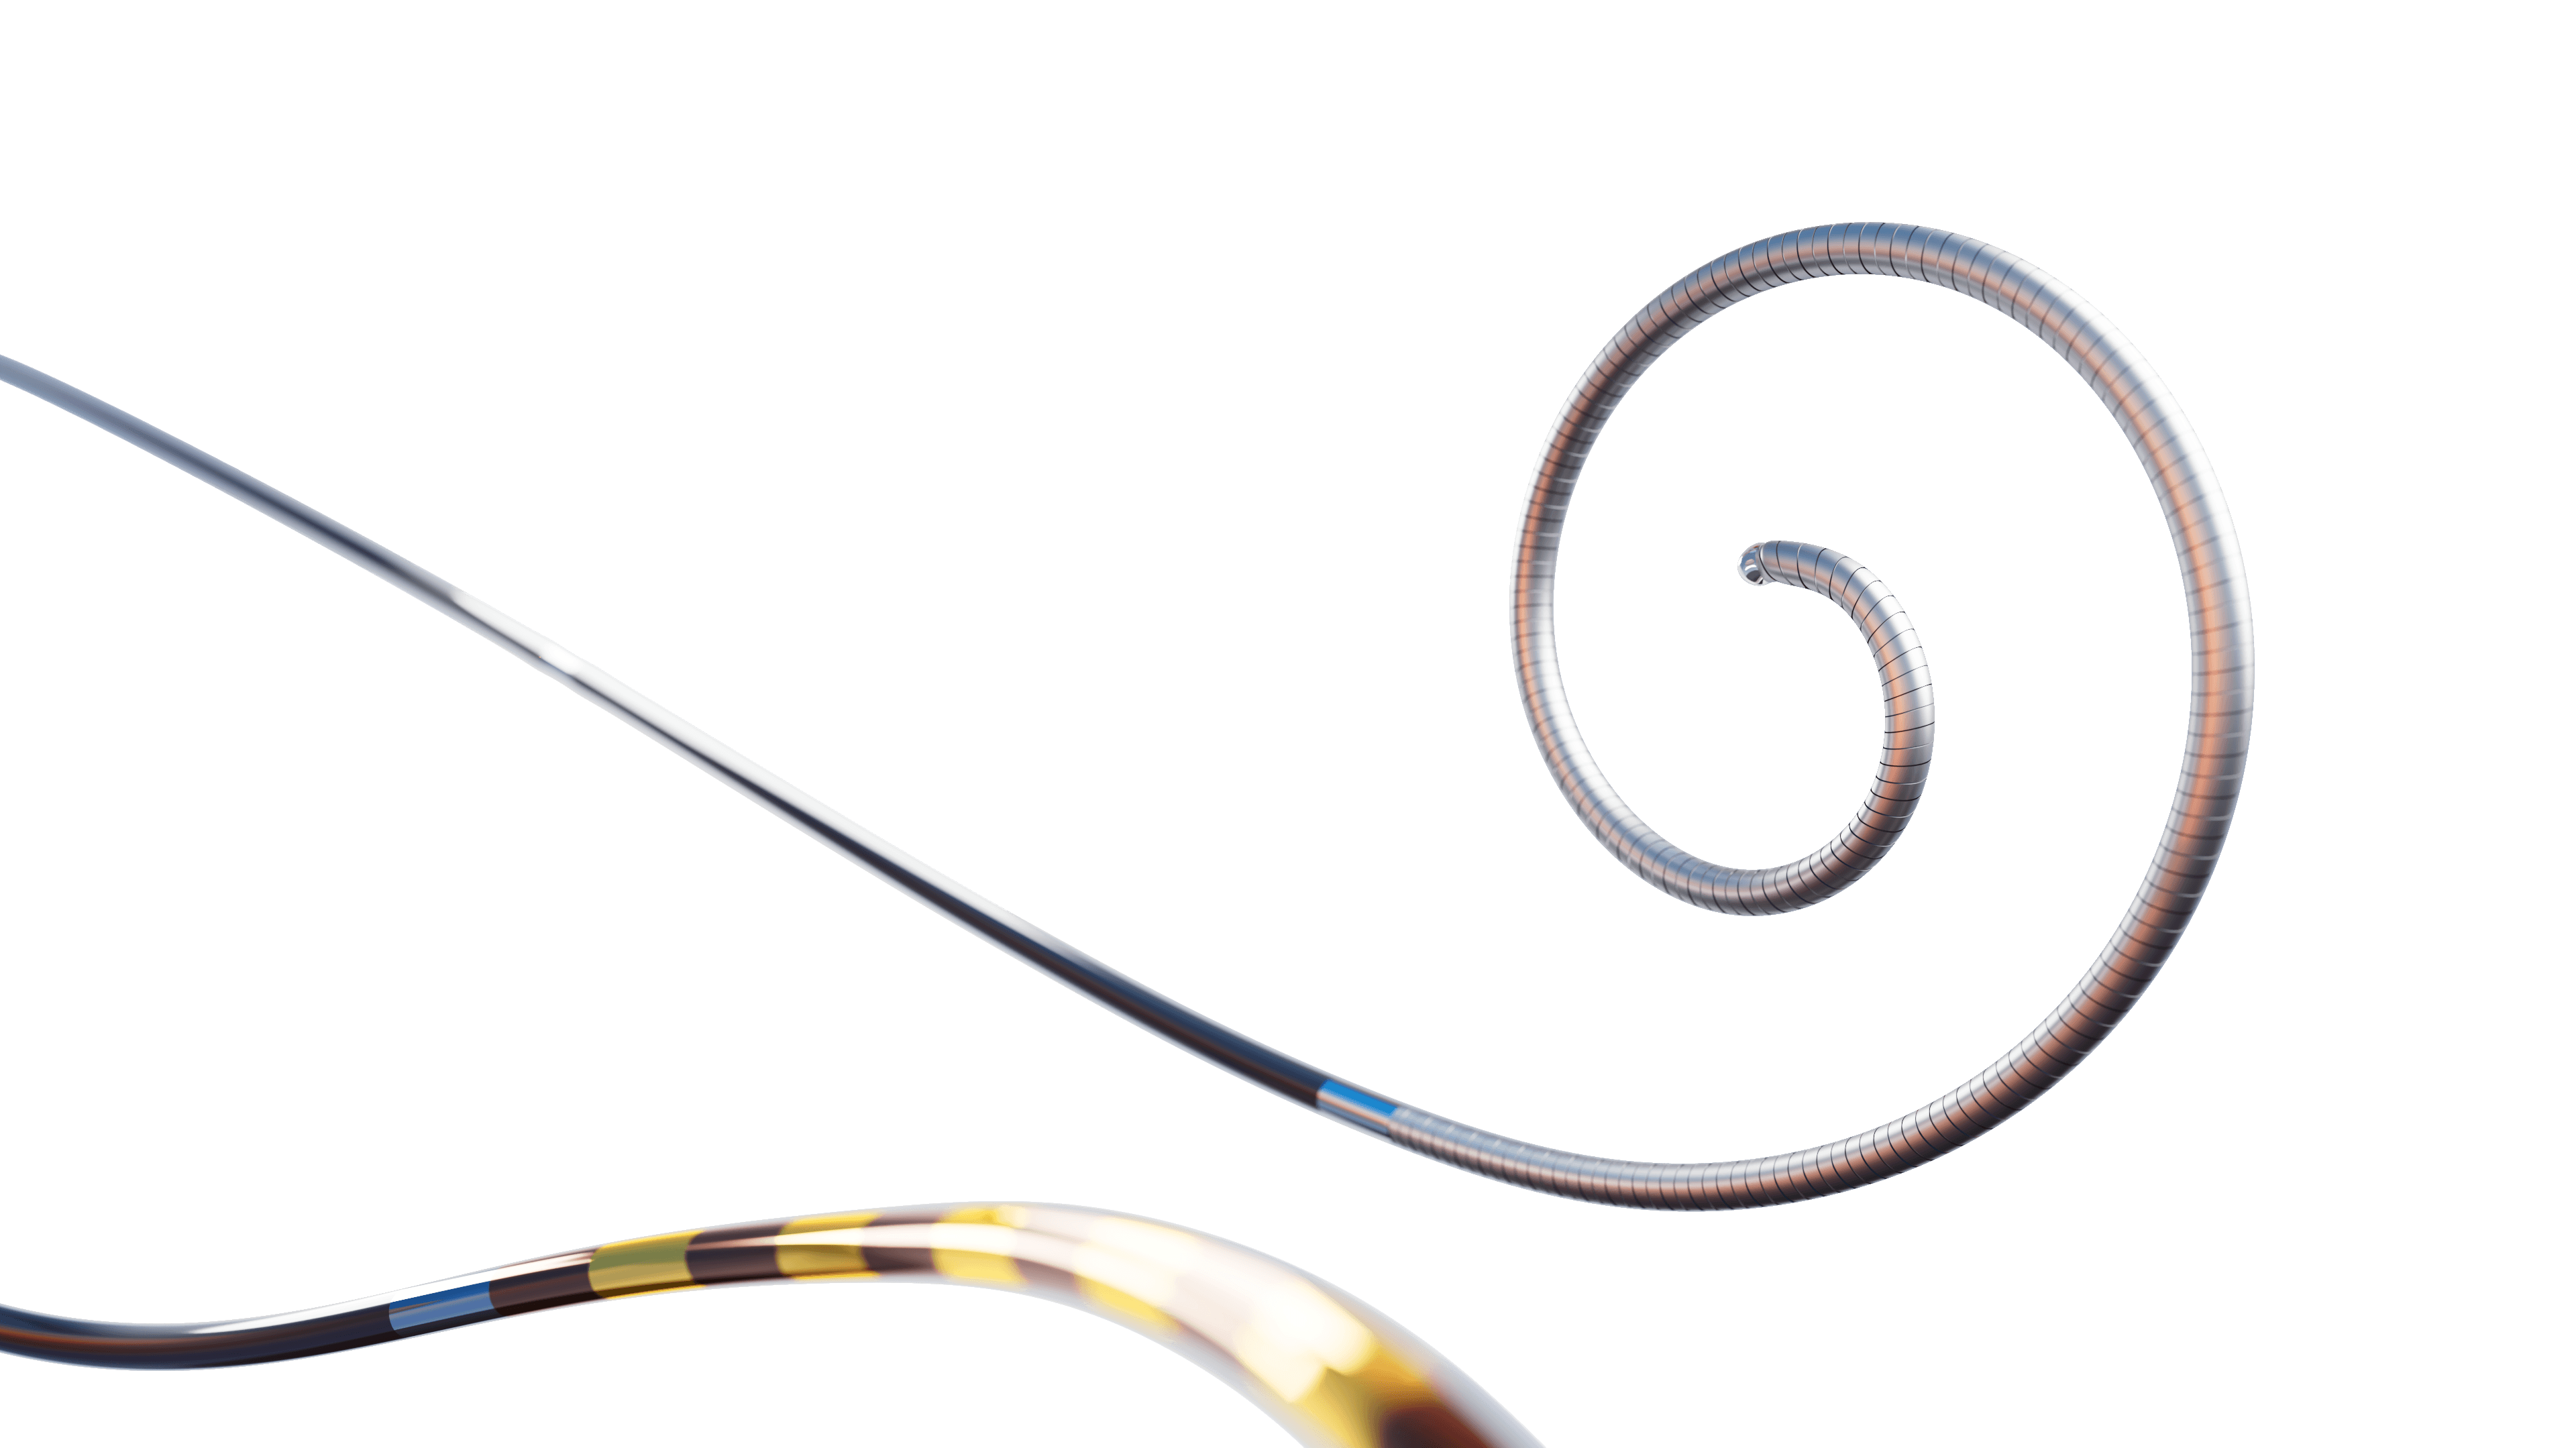

Xenter is infusing novel technologies into workhorse medical devices

Xenter is developing a data-driven platform that embeds wireless capabilities into workhorse devices used to treat and diagnose structural heart, coronary, stroke, vascular disease, cognitive disorders, and more.

Smart Devices

Smart, wireless medical devices

Xenter devices gather Physical Intelligence data from the clinical environment